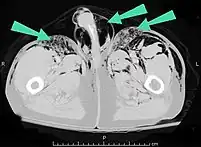

Air can be trapped under the skin in necrotizing infections such as gangrene, occurring as a late sign in gas gangrene,[2] of which it is the hallmark sign. Subcutaneous emphysema is also considered a hallmark of Fournier gangrene.[26] Symptoms of subcutaneous emphysema can result when infectious organisms produce gas by fermentation. When emphysema occurs due to infection, signs that the infection is systemic (i.e. that it has spread beyond the initial location) are also present.[9][21]